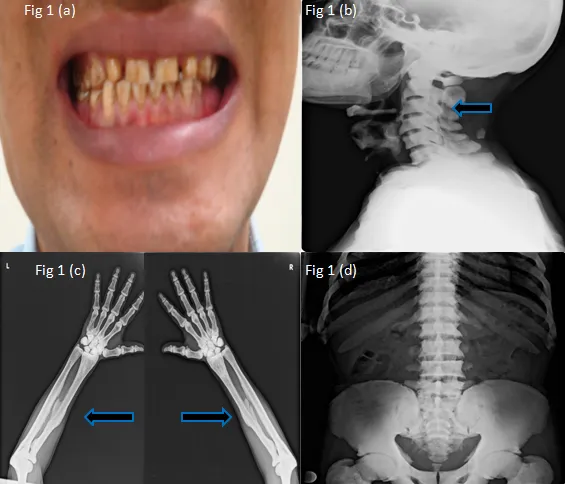

Dental Fluorosis (Earliest sign):

Symmetrical, chalky white opacities, yellow-brown discoloration, pitting.

Dean's Index for Dental Fluorosis:

Score Appearance 0 Normal 1 Questionable (Slight changes) 2 Very Mild (<25% opaque areas) 3 Mild (<50% opaque areas) 4 Moderate (All surfaces, stain) 5 Severe (Hypoplasia, pitting)

Skeletal Fluorosis:

- Phase 1: Sporadic pain, stiffness.

- Phase 2: Constant pain, joint stiffness, osteosclerosis (spine, pelvis).

- Phase 3 (Crippling): Limited movement, kyphosis, flexion contractures, genu valgum/varum.

- Ligament/interosseous membrane calcification.

- Radiography: Key for skeletal fluorosis.

⭐ Radiological findings in skeletal fluorosis include osteosclerosis, osteophytosis, and calcification of ligaments and interosseous membranes (e.g., forearm, pelvis).

- Skeletal fluorosis features osteosclerosis, osteophytes, and ligamentous/tendon calcification (enthesopathy).

- Dental fluorosis presents as mottled enamel (chalky white to brown stains).

- Key X-ray signs: ↑ bone density, calcification of interosseous membrane (forearm, leg).